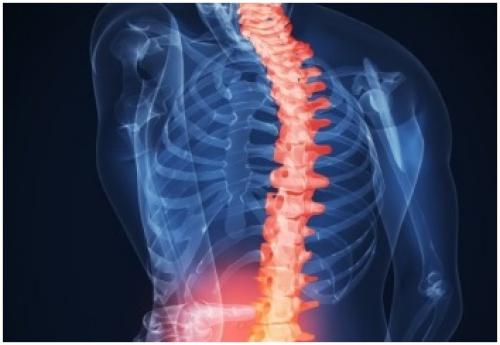

Препарат для хрящевой ткани. Почему назначаются уколы?

Установлено, что медикаментозные препараты в виде инъекций действуют быстрее, чем остальные лекарственные формы. Поэтому в случае ярких проявлений нарушения целостности хрящевой ткани и сильной боли назначаются новейшие восстановительные препараты в инъекциях, причём, такие лекарства могут применяться даже на второй стадии заболевания суставов или позвоночника.

Препараты для восстановления хрящевой ткани позвоночника. Как восстановить хрящевую ткань позвоночника?

Восстановление хрящевой ткани позвоночника возможно за счет приема хондропротекторов, витаминов, гормональных средств. Плюс к медикаментам идет нормализация питания и полный отказ от табакокурения и алкоголя. Начинать лечение не рекомендуется без ведома специалиста.

Почему происходит разрушение хрящевой ткани?

Разрушение хрящевой ткани настигает чаще всего людей в возрасте, работающих физически и тех, кто систематически получает травмы (боксеры, каратисты, любители драк и др.).